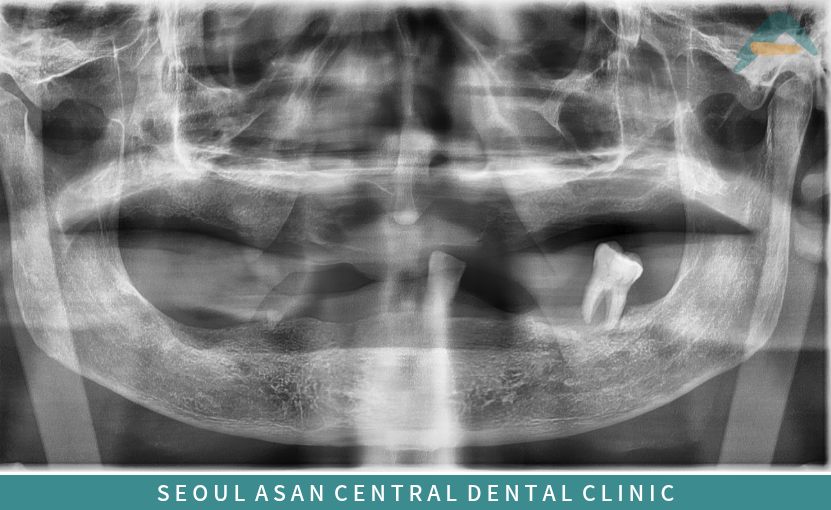

수정구치과 서울아산센트럴에서는

틀니 제작 전 잇몸의 높이와 형태,

저작 근육의 움직임,

남아 있는 치아의 상태와 위치 등

구강 전반의 상태를 꼼꼼하게 확인한 뒤

정밀하게 잇몸 모양을 본떠

개인에게 맞는 틀니 제작을 진행하고 있습니다.

이 과정에서 구강 구조와

기능적인 부분까지 함께 고려하여

보다 안정적으로 사용할 수 있도록

도움을 드리고 있습니다.